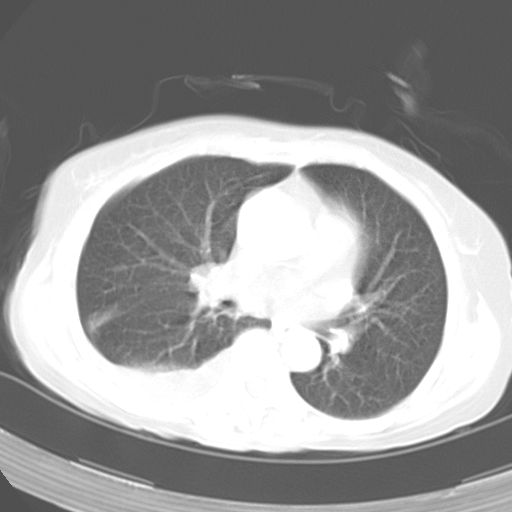

以下是引用dyqct在2006-12-7 21:08:00的发言:[br]考虑:1、肝内外胆管多发性结石伴肝左叶外侧段肝萎缩;[br] 2、右膈下多发脓肿;[br] 3、右侧少量胸腔积液、斜裂积液;[br] 4、左肾囊肿。

以下是引用jiazh在2006-12-7 20:37:00的发言:[br]肝脏周围半狐形低密度影,肝脏表面受压推移,考虑膈下脓肿可能性大;2、右侧胸腔积液

以下是引用拾荒者在2006-12-7 21:44:00的发言:[br]肝内外胆管多发结石,右膈下多发脓肿,右胸膜腔及叶间裂积液,左肾囊肿。[br] [br]